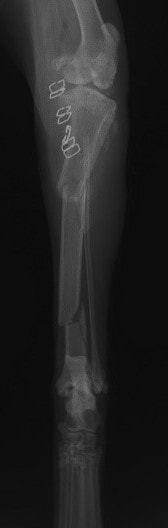

症例3:キルシュナーワイヤーのピンニングによる整復

ペルシャ猫 11ヶ月齢 雄

他院にて左大腿骨遠位の成長板骨折(salter-harrisⅠ型)が認められており、治療相談を目的として来院。当院にて、キルシュナーワイヤーを用いたピンニングにより骨折部位の整復を行いました。術後の経過は良好で、現在も経過観察中です。

術前レントゲン

術後レントゲン

Arthrex社のターゲティングデバイスを用いてピンニングの位置を調整することで、確実な固定を行っています。当院ではこの手術器具以外にも、人の手術にも使用される様々な器具を導入し、手術精度を高め、また医療メーカーと新しい器具の開発、試作にも取り組んでおります。